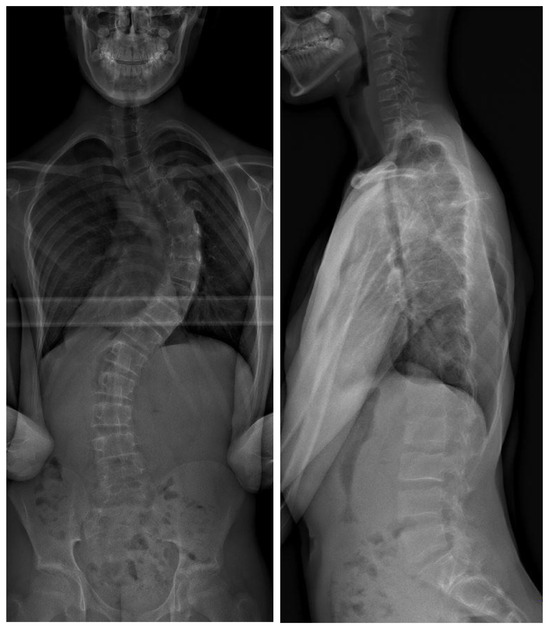

Figure 2.

Biplanar radiograph of the same patient after posterior instrumented fusion using freehand technique. The intraoperative DAP was 638.2 mGy/cm2.